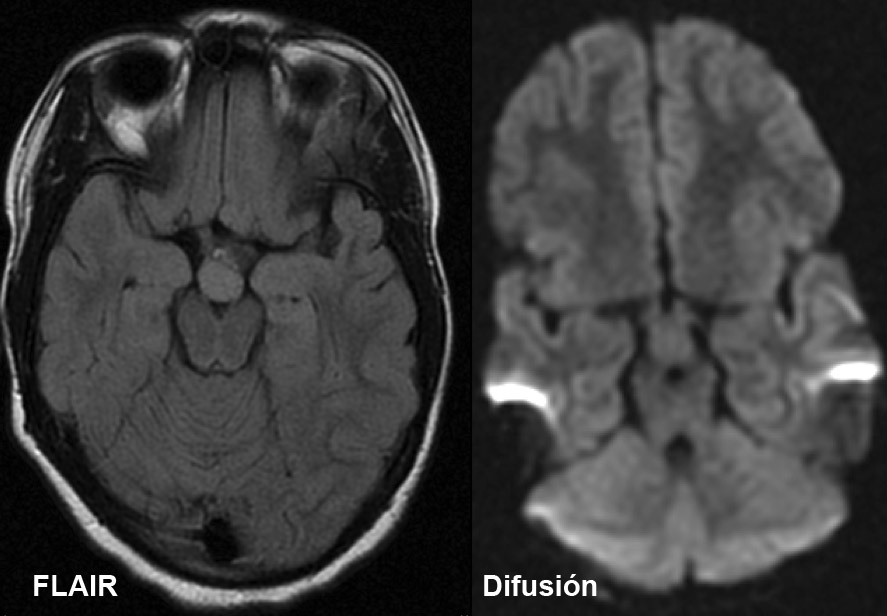

Niña de 7 años. Se solicita RM hipofisaria por pubertad precoz.

1. ¿Cuál es tu diagnóstico?

- A. Glioma hipotalámico.

- B. Histiocitosis X.

- C. Hamartoma hipotalámico.

- D. Craneofaringioma.

- E. Germinoma hipotalámico.